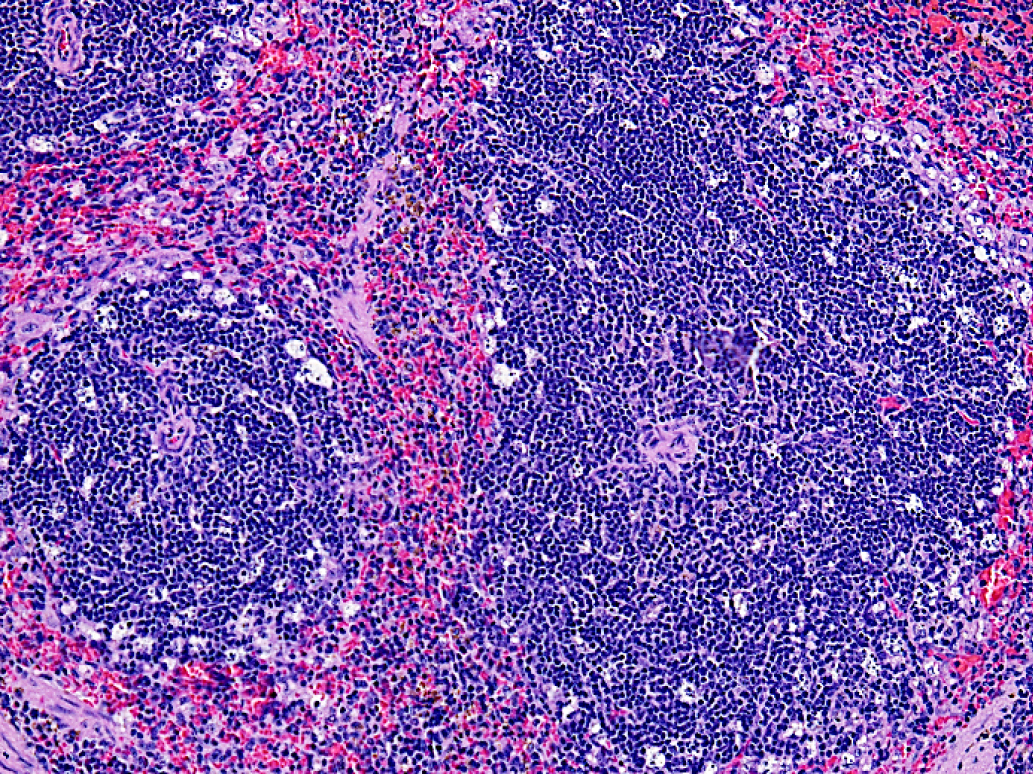

В селезенке подопытных животных регистрировали многочисленную гибель лимфоидных клеток по периферии фолликулов белой пульпы (рис. 4).

Рис. 4. Фрагмент селезенки подопытной мыши после введения 5'- нораристеромицина в дозе 80 мг/кг. Окраска гематоксилином-эозином. Увеличение 200